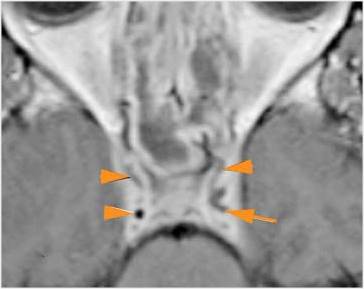

There is evidence of thrombus, thrombophlebitis or other occlusive or inflammatory process of the cavernous sinus. [Yes/No]

There is evidence of inflammation of the distal internal carotid artery. [Yes/No]

There is evidence of an infectious aneurysm. [Yes/No]

There is brain edema specifically involving the frontal and temporal lobes. [Yes/No]

There is cerebritis specifically involving the frontal and temporal lobes. [Yes/No]